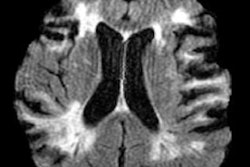

The prototype MRI scanner identified most key pathologies in all 25 patients, compared with the conventional 3-tesla scanner: In one brain tumor case, both the 0.055-tesla and conventional MRI images showed a mass in the right parietal cortex that was "hypointense in T1W and hyperintense in T2W," the group wrote. The study also demonstrated the following:

- T1W images on both types of MRI scanners showed clear asymmetry between the right and left hemisphere, indicating a cystic lesion.

- The prototype scanner showed "excellent sensitivity and correspondence" with the conventional scanner in identifying a choroid plexus cyst at the occipital horn of the right lateral ventricle.